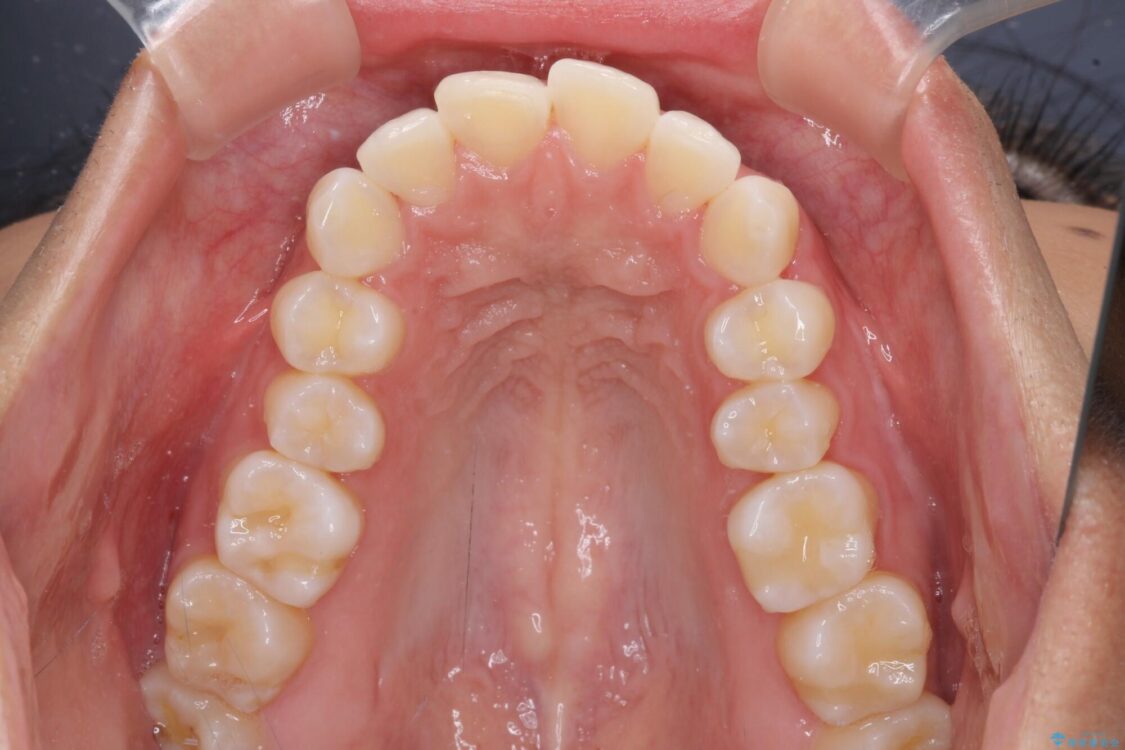

治療後

• 抜歯矯正で唇を閉じやすく 目立たないワイヤー装置 治療後画像